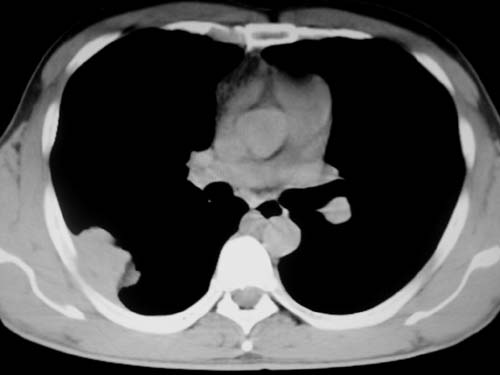

标题: CT19540: 31岁。自述结核性胸水治疗两个月后,在外院拍x线发 [打印本页]

标题: CT19540: 31岁。自述结核性胸水治疗两个月后,在外院拍x线发

右侧胸壁结节状软组织影伴相应肺叶内受侵,伴右侧胸腔积液。考虑:结核性可能大。

以下是引用王显瑞在2009-4-23 8:38:00的发言:[br]右侧胸壁结节状软组织影伴相应肺叶内受侵,伴右侧胸腔积液。考虑:结核性可能大。

支持 右侧胸壁结节状软组织影伴相应肺叶内受侵,伴右侧胸腔积液。考虑:结核性可能大。

右侧胸壁结节状软组织影伴相应肺叶内受侵,伴右侧胸腔积液,结合临床,首先考虑结核。

考虑结核性胸膜炎,胸膜肥厚,不除外胸膜间皮瘤可能,建议复查。

1)考虑右侧结核性胸膜结节。2)右侧胸膜增厚+包裹性胸腔积液。